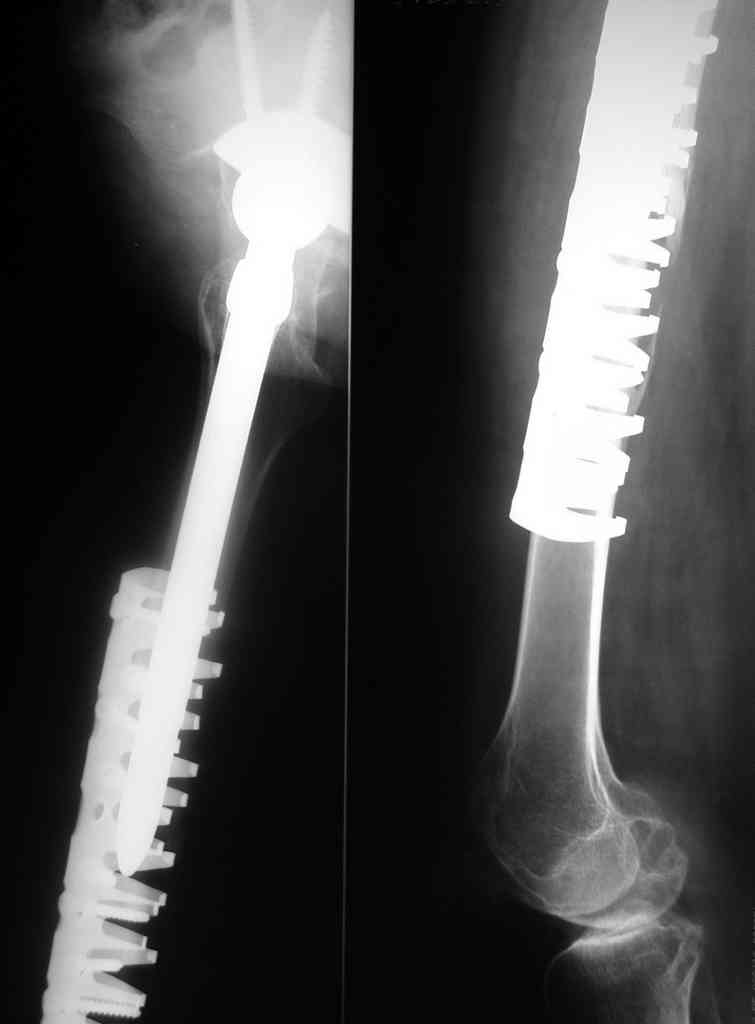

В июне 2006 года в ДТП была сбита автомобилем и получила поперечный оскольчатый околопротезный перелом в с/з диафиза бедра, с сохранением стабильности ножки протеза. Через 2 недели после травмы в клинике был произведен открытый остеосинтез бедра пластиной Bridge Plate DePuy. Больная ходила с костылями, через 3 месяца после остеосинтеза начала постепенно увеличивать нагрузку на ногу.

Через 6 месяцев клинически и на контрольных рентгенограммах было выявлена деформация бедра. Планируется провести реостеосинтез бедра аналогичной пластиной большей длины с применением костной аутопластики и (или) материалов типа MIIG, IGNITE, ALLOMATRIX.

Хотелось бы услышать мнение по альтернативной дальнейшей тактике лечения данной больной и узнать о результатах применения Bridge Plate в других клиниках

June 2006 - in a car accident sustained periprosthetic shaft fracture. Two weeks later ORIF with Bridge Plate (DePuy) was performed. 3 month on crutches, then started to increase weight-bearing. 6 month later the deformation was obvious. The current plan is to perform ORIF with longer plate og the same design with bone grafting and/or bone substitutes like MIIG, IGNITE, ALLOMATRIX. Is the plan reasonable, maybe any alternative exists? Any other treatment modalities? Can somebody share results of such Bridge plating? THX for your suggestions. С уважением Василий Бабушкин.